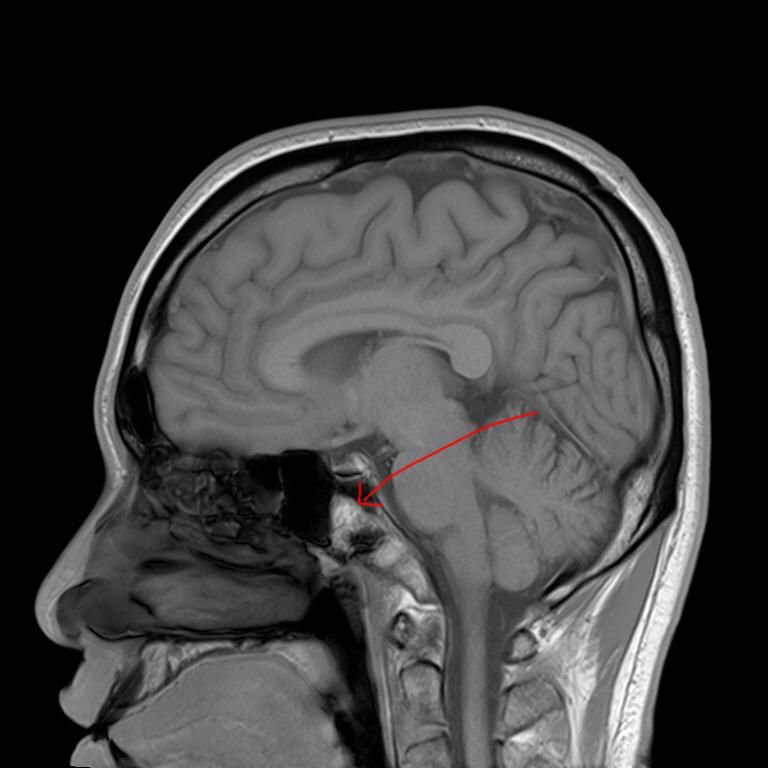

mri 사진을 봤을 때 정확히 어디가 막힌 걸까요? 그리고 치료는 할 수 있는 걸까요???

• 3번 째 사진

올려주신 영상 관련 보다 더 자세한 분석 원하시면 영상의학과 전문의한테 물어보셔야 해요

말씀하신 증상 관련 답변 드리자면 15년동안 지속된 귀와 코 사이 막힘 증상은 이관(유스타키오관) 기능 장애일 가능성이 높습니다. 진한 콧물을 강하게 들이마신 후부터 증상이 생겼다면, 이관이 분비물이나 압력 변화로 막히거나 손상되었을 가능성이 있습니다. 이관은 코 뒤쪽과 귀 중이를 연결하는 통로로, 막히면 귀먹먹함, 압력감, 울림 증상 등이 지속될 수 있습니다. MRI나 CT를 통해 이관 주변 구조(비인두, 부비동, 중이강 등)의 해부학적 이상을 더 정확히 확인해야 합니다.

현재는 내시경, 고해상도 CT, 이관 기능검사 등 진단 기술이 과거보다 훨씬 정밀해졌고, 증상에 따라 이관 풍선확장술, 내시경 하 비인두 수술 등 다양한 치료 방법이 가능해졌습니다. 15년이 지나도 충분히 치료 가능성이 있으니, 이비인후과 중에서도 두개저, 이관 관련 전문의가 있는 병원을 찾아 재평가 받는 것이 좋습니다.